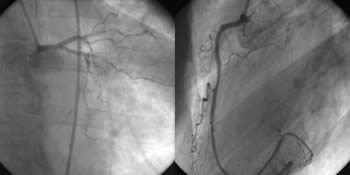

Fig. 2: CAG in a patient with ST-elevation myocardial infarction.

Semiquantitative CAG description (used in most routine settings):

Distal RCA 90% with thrombus. Left coronary artery normal.

Qualitative + semiquantitative CAG description (as used in our center): Right dominant coronary type. Coronary ectasias involving entire right coronary artery and proximal segment of the left circumflex artery. Large partially occlusive intraluminal thrombus, probably without pre-existing significant stenosis in the largest aneurysmatic segment of the RCA. Due to the likely absence of pre-existing stenosis and extremely large RCA diameter (> 6 mm) no PCI is recommended and treatment by intracoronary GP IIb/IIIa inhibitor should be used.